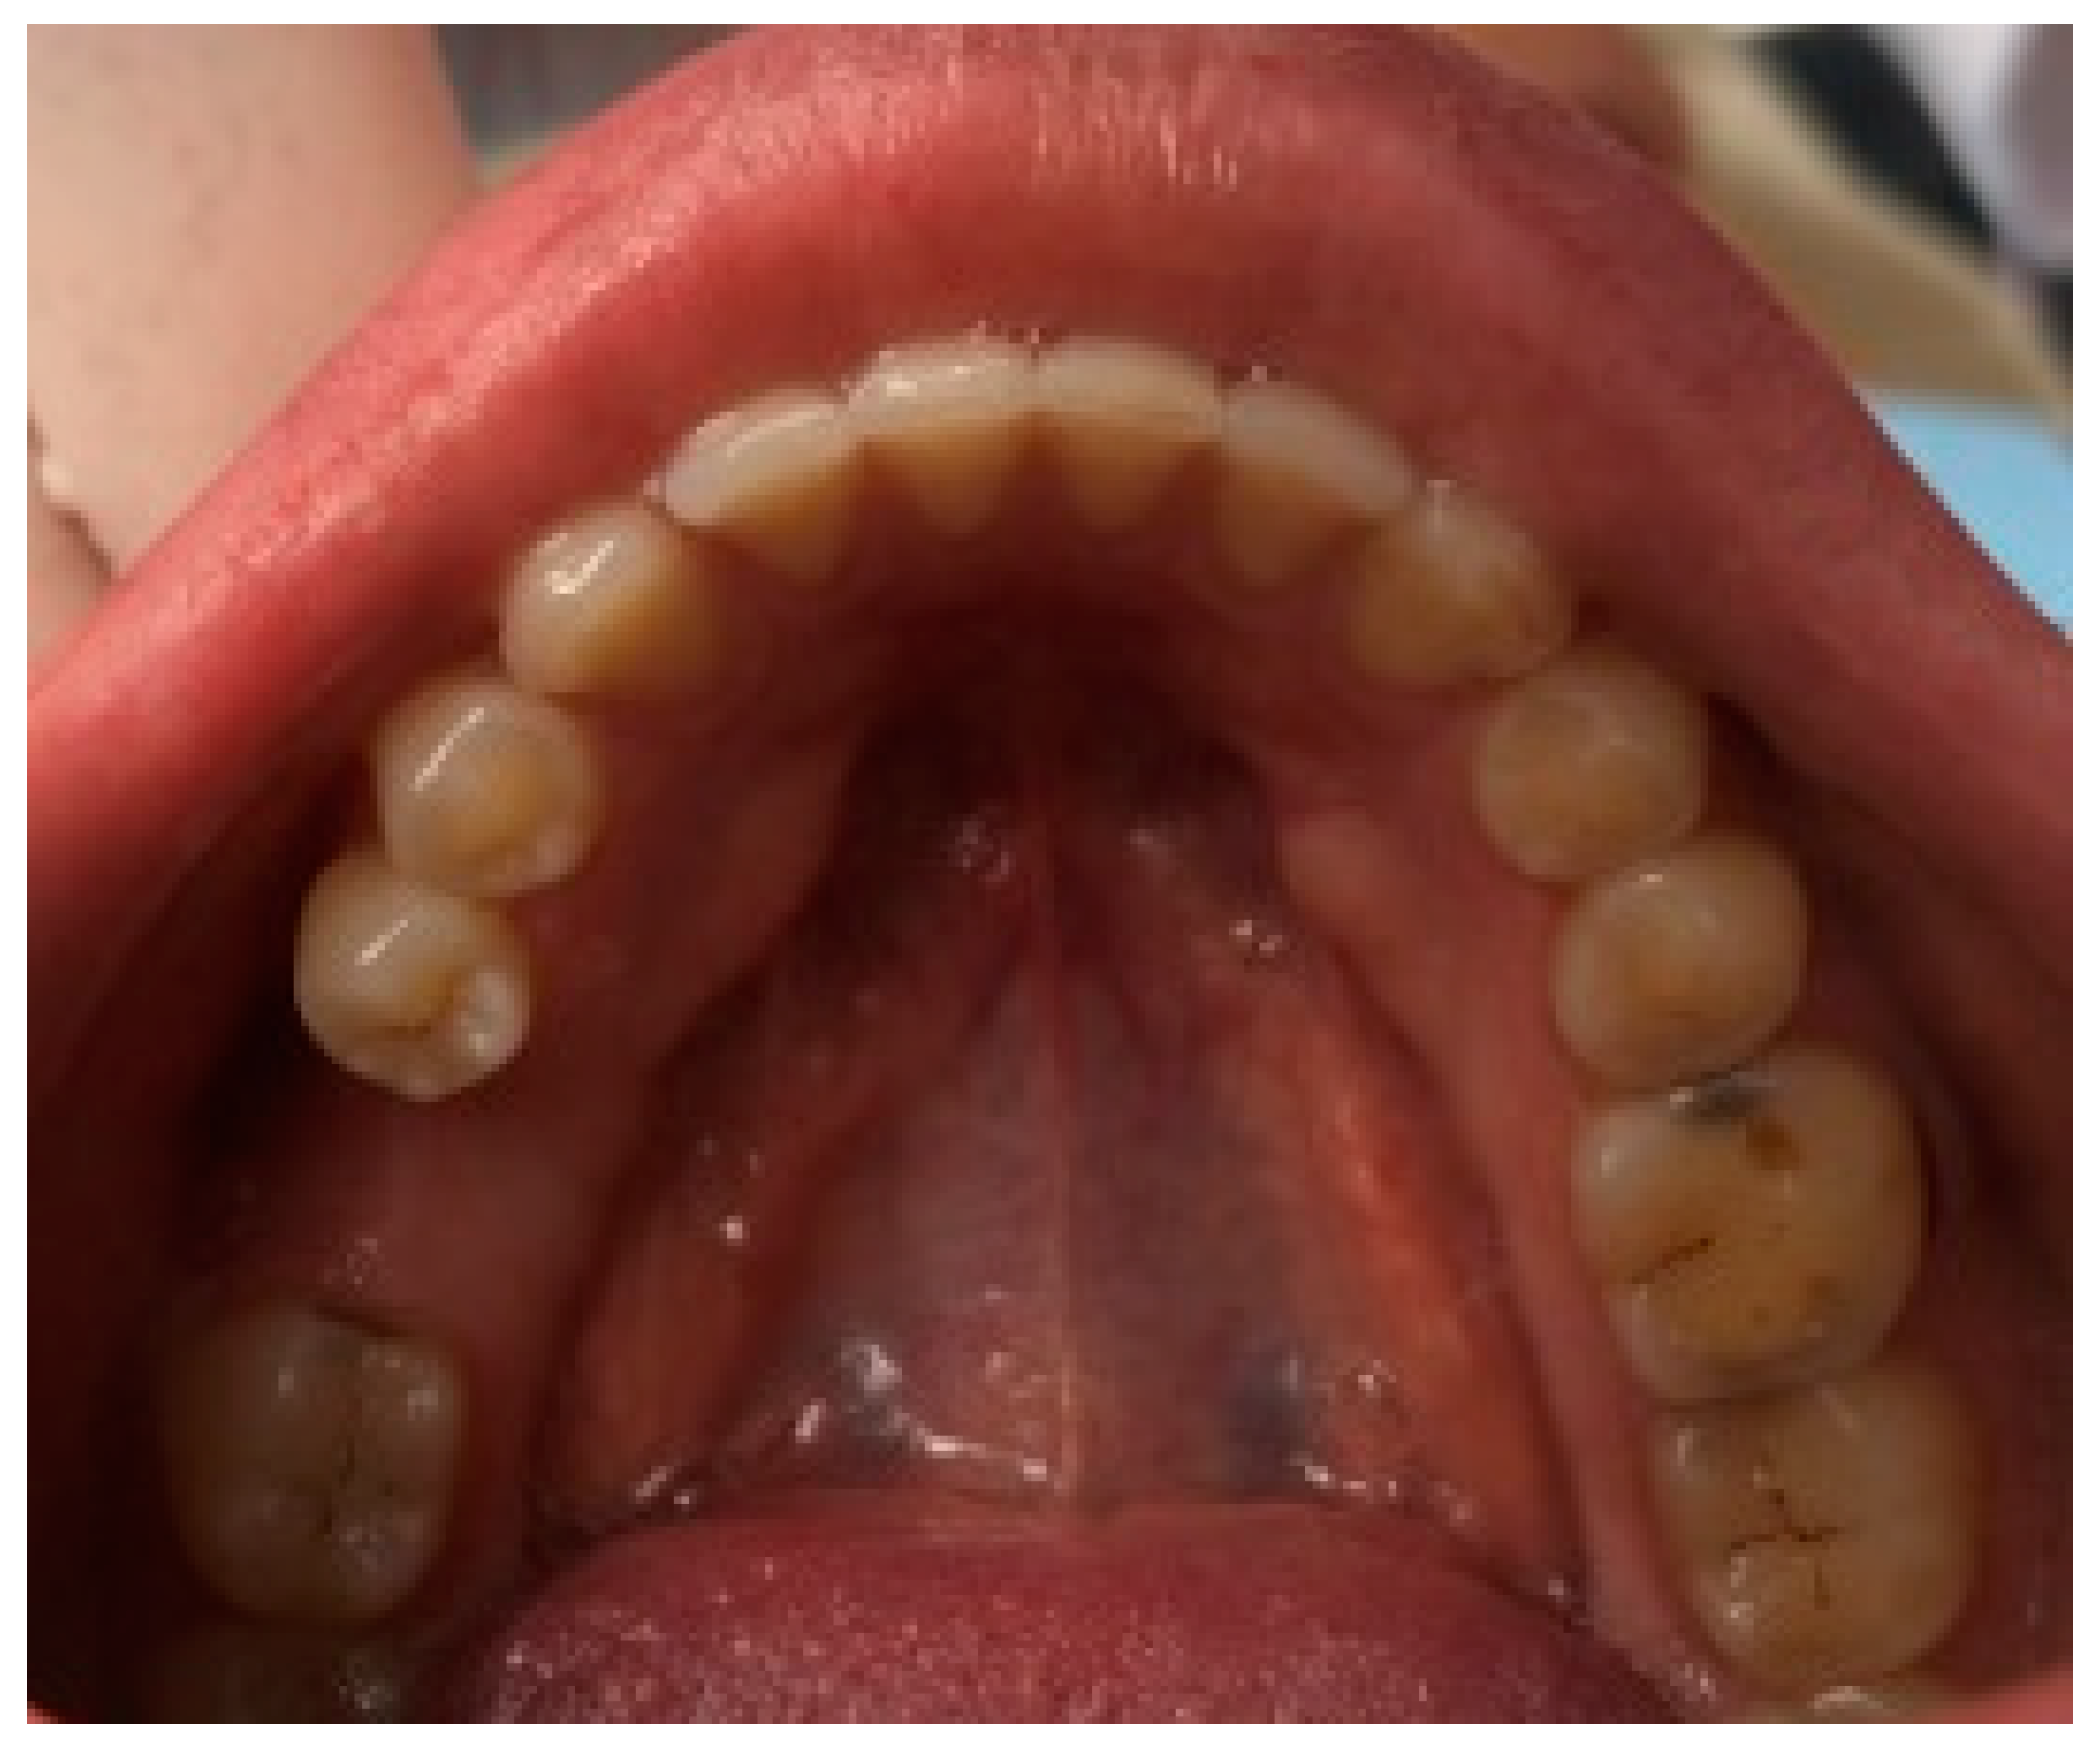

| Torus palatinus (TP) | 14 (11.5) |

| Torus palatinus | 11 (14.3) | 3 (6.7) | 14 (11.5) | 0.466 |

| Flat | 7 (63.6) | 3 (100.0) | 10 (71.4) | |

| Spindle-shaped | 2 (18.2) | 2 (14.3) | ||

| Nodular | ||||

| Lobular | 2 (18.2) | 2 (14.3) | ||